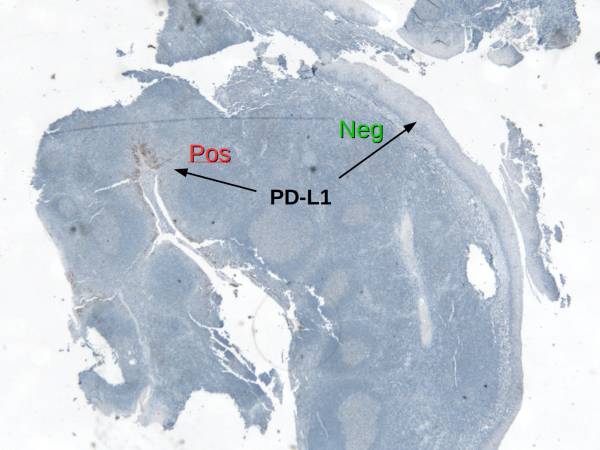

PDL1 Expression by Squamous Epithelium (Tonsil) protecting itself within a cryptitis

At low magnification (Left), one sees the heterogeneous expression of PDL1 in a tonsil which is used as a preferred positive on-slide control for PDL1. This expression is explained by a focal invasion of T cells reaching an infectious area (Center: DAB: CD3, RED: Cytokeratin). The T cells release Interferon-Gamma which stimulates local expression of PDL1 by the epithelium. The right picture shows PDL1 expression at higher magnification.